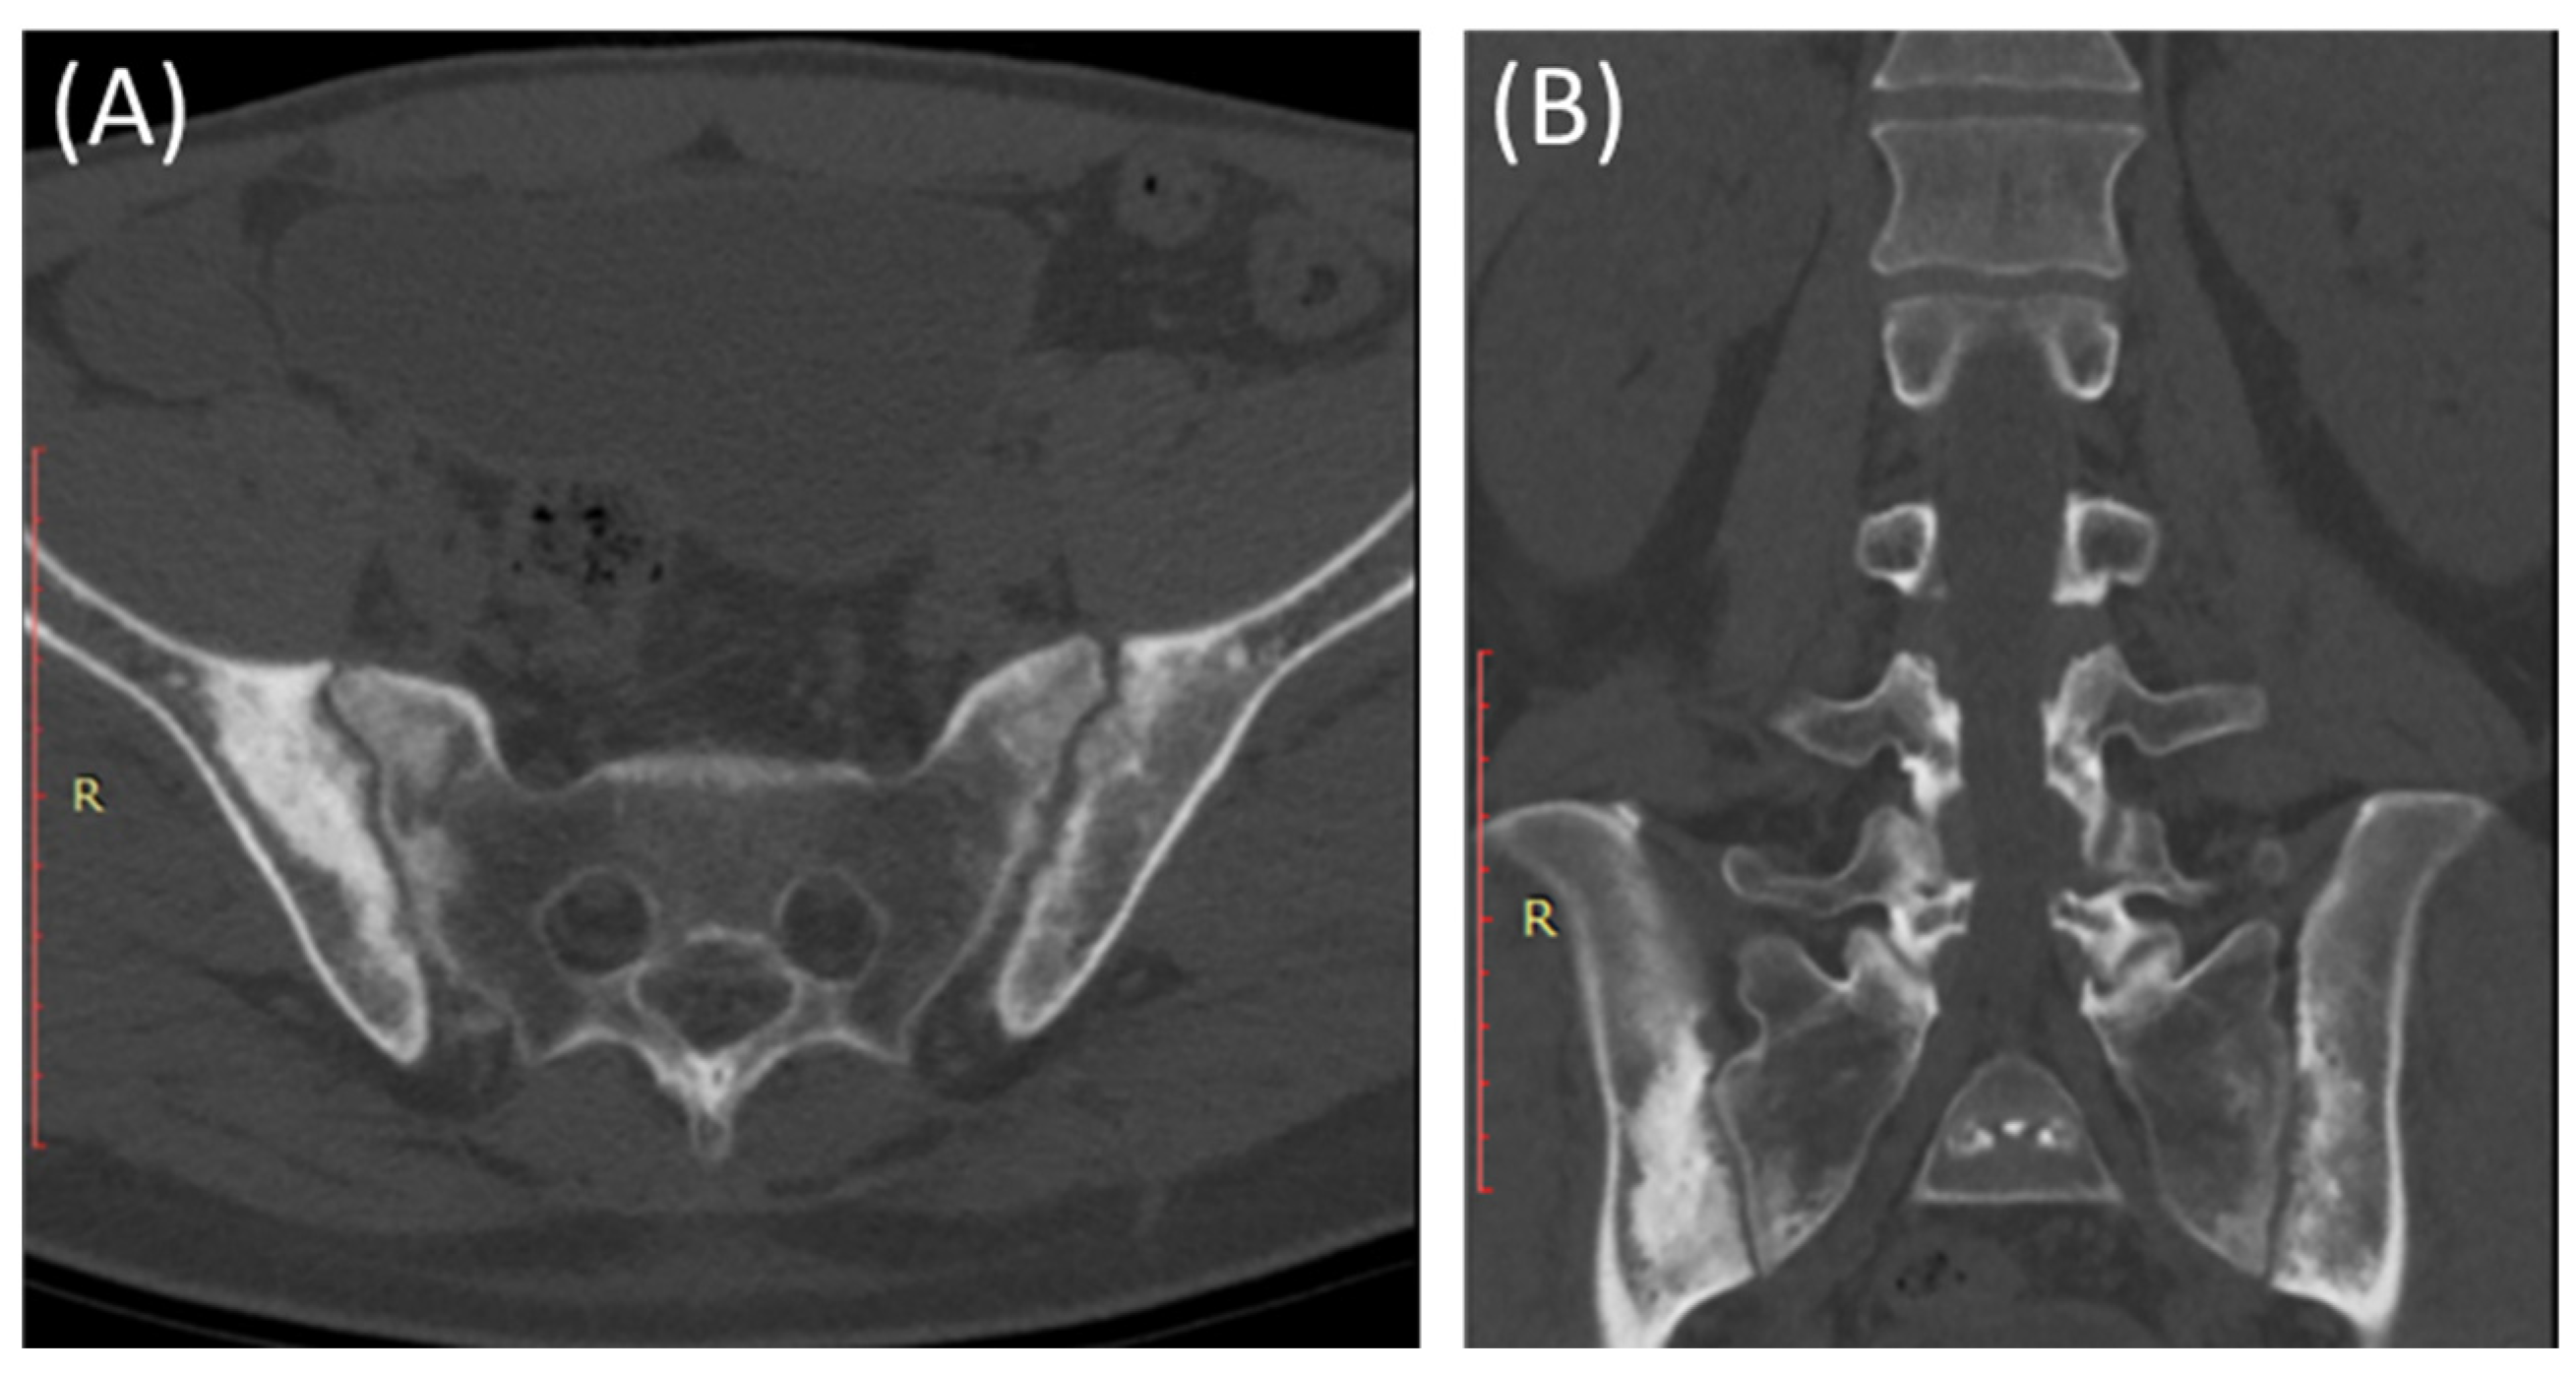

CT scans provide more detailed images of the sacroiliac joint and can reveal erosions, sclerosis, and joint space narrowing with greater clarity than X-rays [13]. Severe sacroiliitis, particularly in cases of ankylosing spondylitis, can lead to complete fusion or ankylosis of the sacroiliac joint [4]. CT scans can demonstrate the fusion as a solid, bony bridge between the sacrum and ilium [4]. CT scans can also assess soft tissues surrounding the SIJ, such as ligaments, tendons, and muscles, which may be inflamed in cases of sacroiliitis [44] as demonstrated in Figure 4 and Figure 5.

Figure 4.

Axial bone window CT scan (A) and coronal bone window CT scan (B) for a 41-year-old male presenting with Rt sciatica suggestive of bilateral sacroiliitis (same Patient as in Figure 3).

Figure 5.

Axial bone window CT scan (A) showing Chronic sacroiliitis with ankyloses of the sacroiliac and a sagittal bone window CT scan (B) showing Syndesmophytes in the spine in a 55-year-old patient with Ankylosing spondylitis.